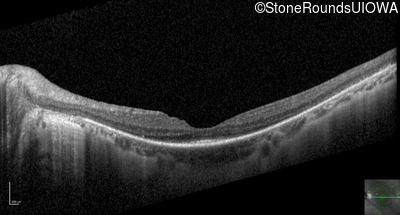

Optical Coherence Tomography - Right - 20/40 +1

Exemplar / OCT Stack